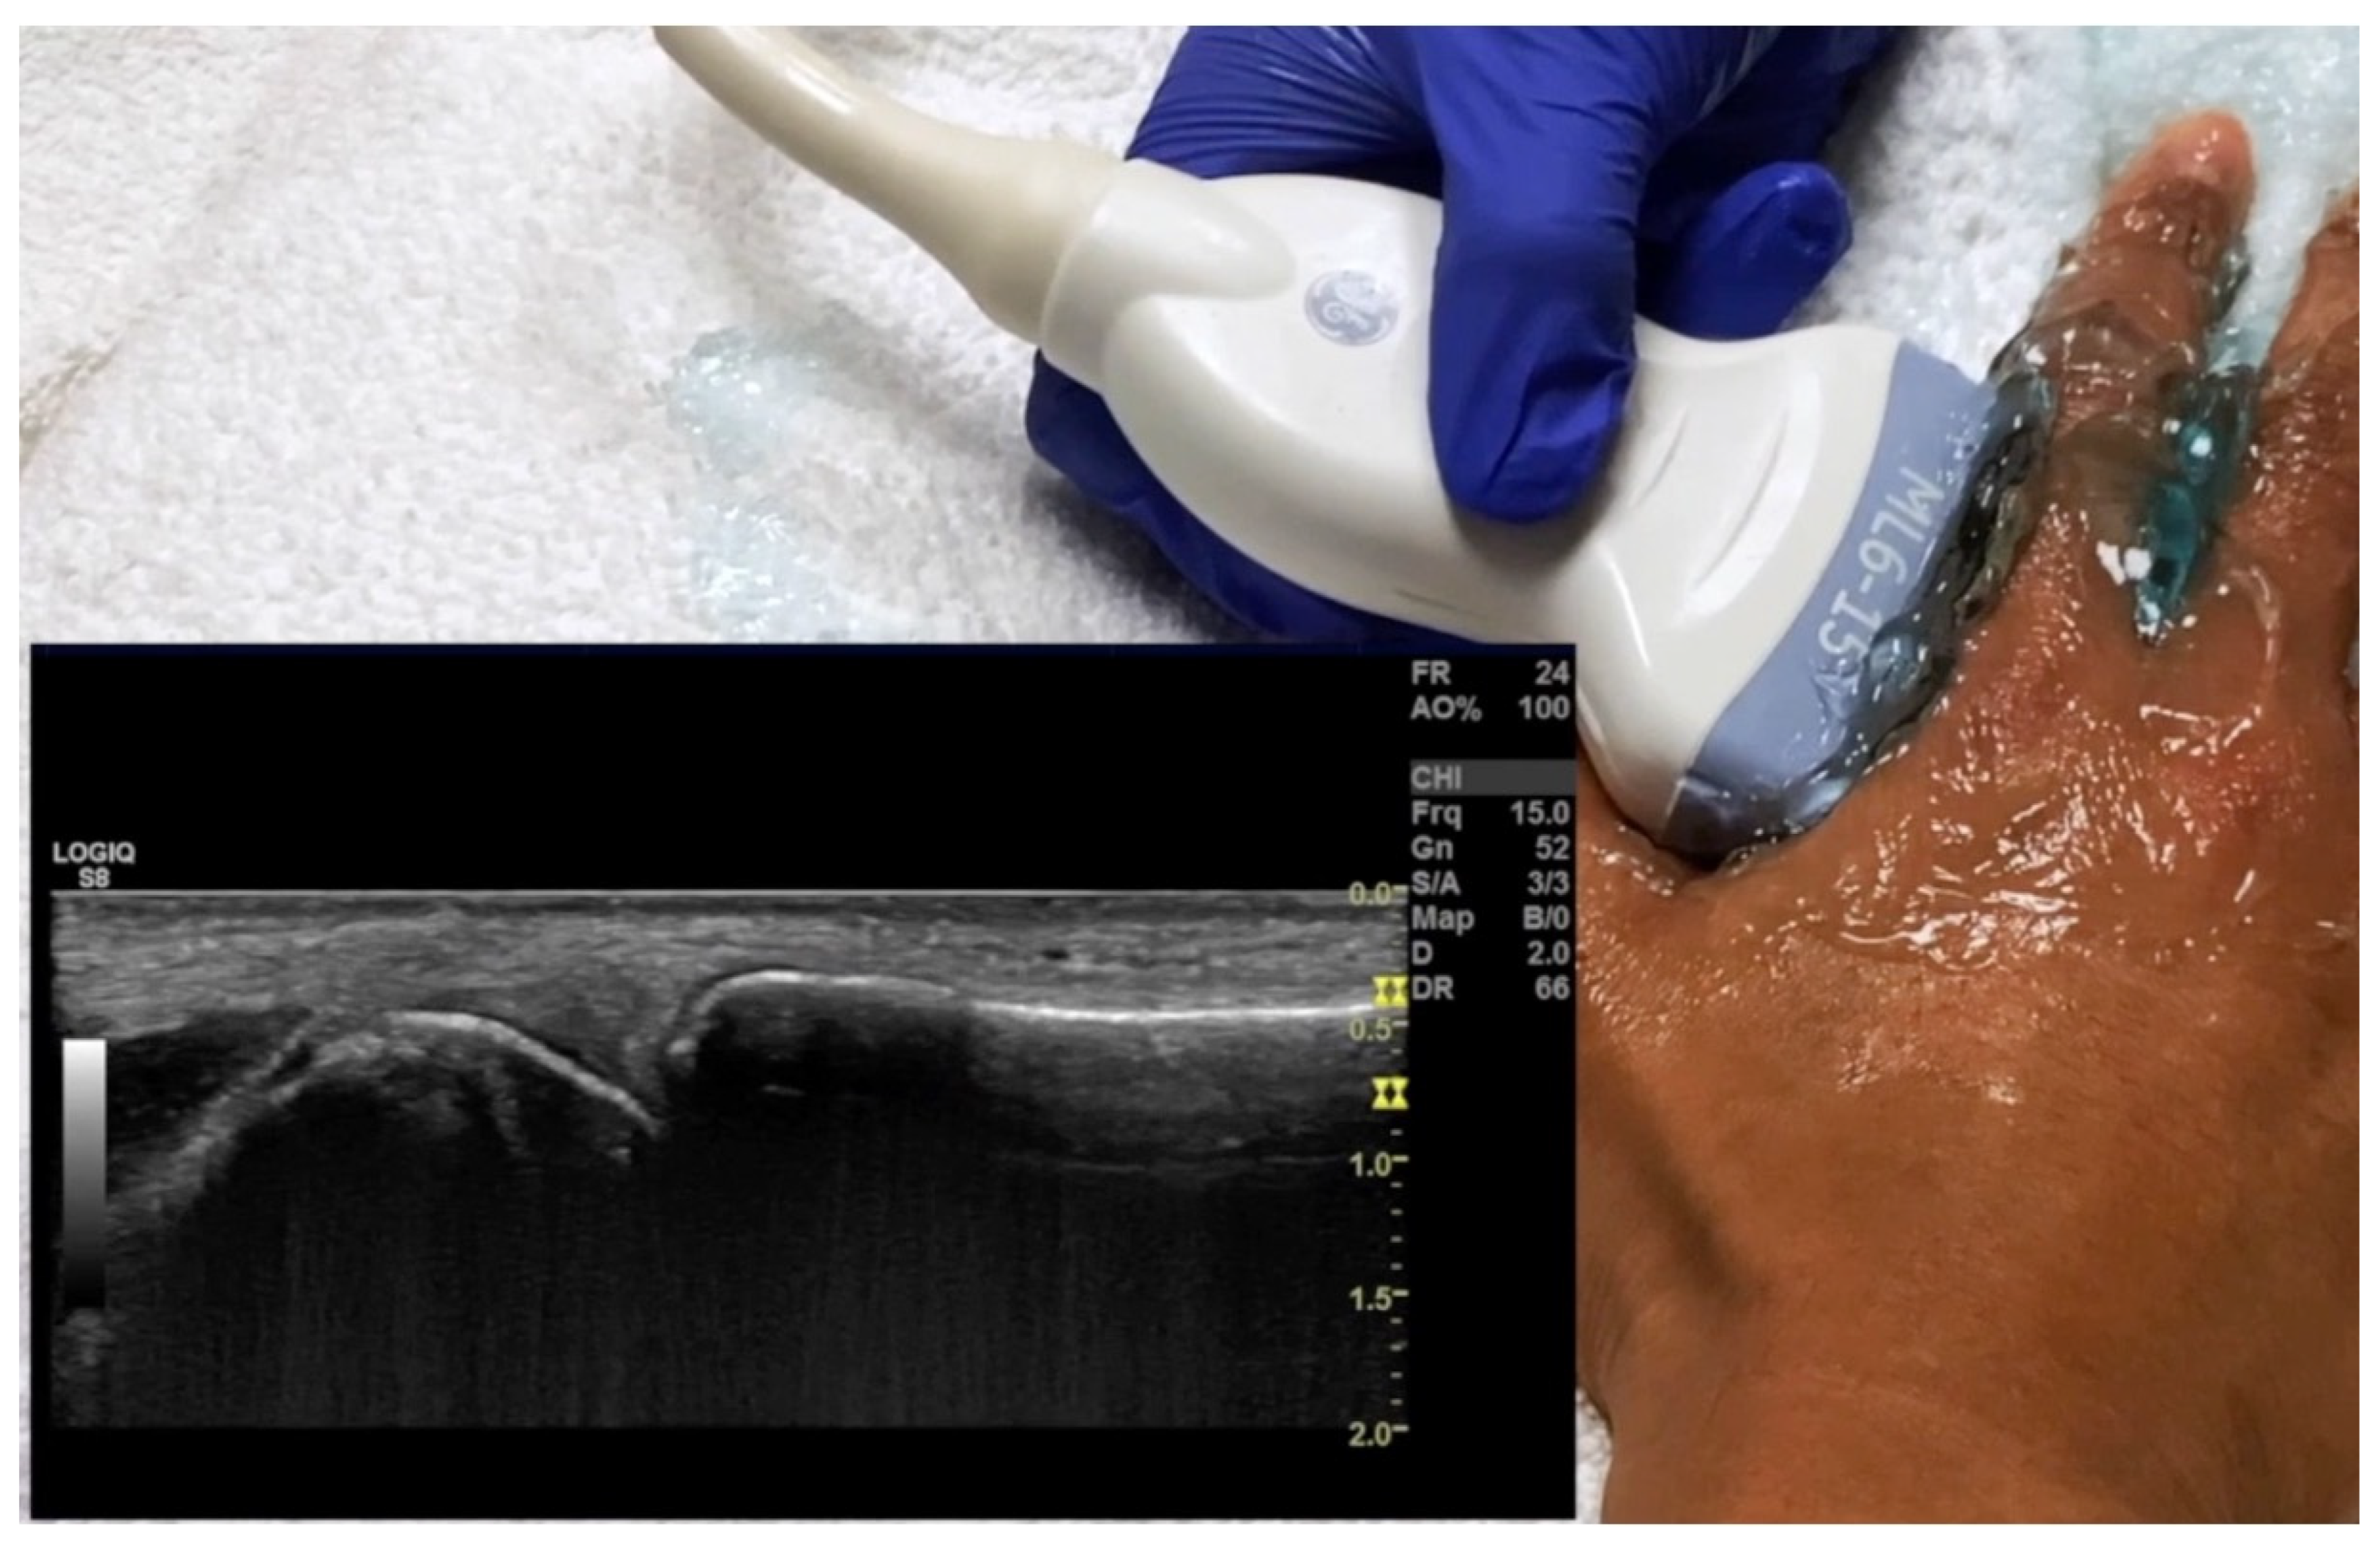

4.1. Evaluation of the Fingers

4.1.1. Dorsal Aspect

4.1.2. Volar Aspect

4.1.3. Radial and Ulnar Aspects